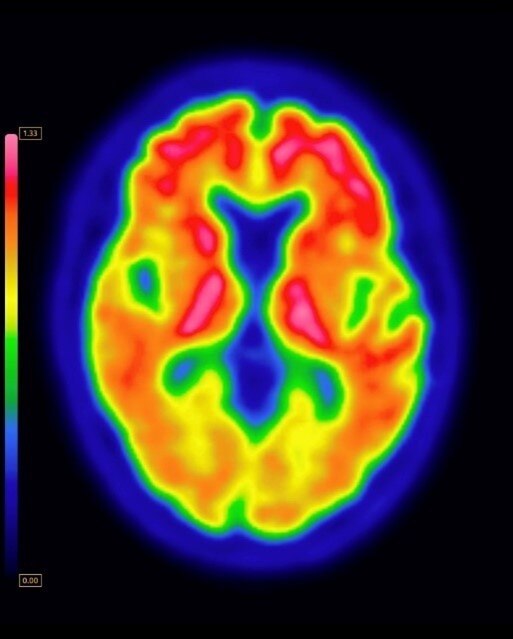

Vizamyl

Download